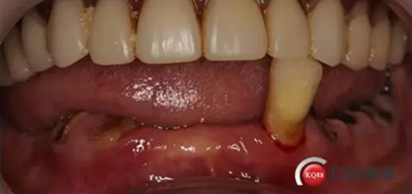

檢查:上頜無(wú)牙頜假牙穩(wěn)定性尚可,下頜3435364243殘根;33殘冠1-2度松動(dòng),其他牙齒缺失;CBCT檢查:下頜牙槽骨前牙區(qū)骨高度足,后牙區(qū)骨高度最低為8mm,骨寬度足。

1)術(shù)前檢查,拍攝臨床照片及CBCT檢查,制取活動(dòng)義齒參考模型,指導(dǎo)后期最終修復(fù)的牙齒排列